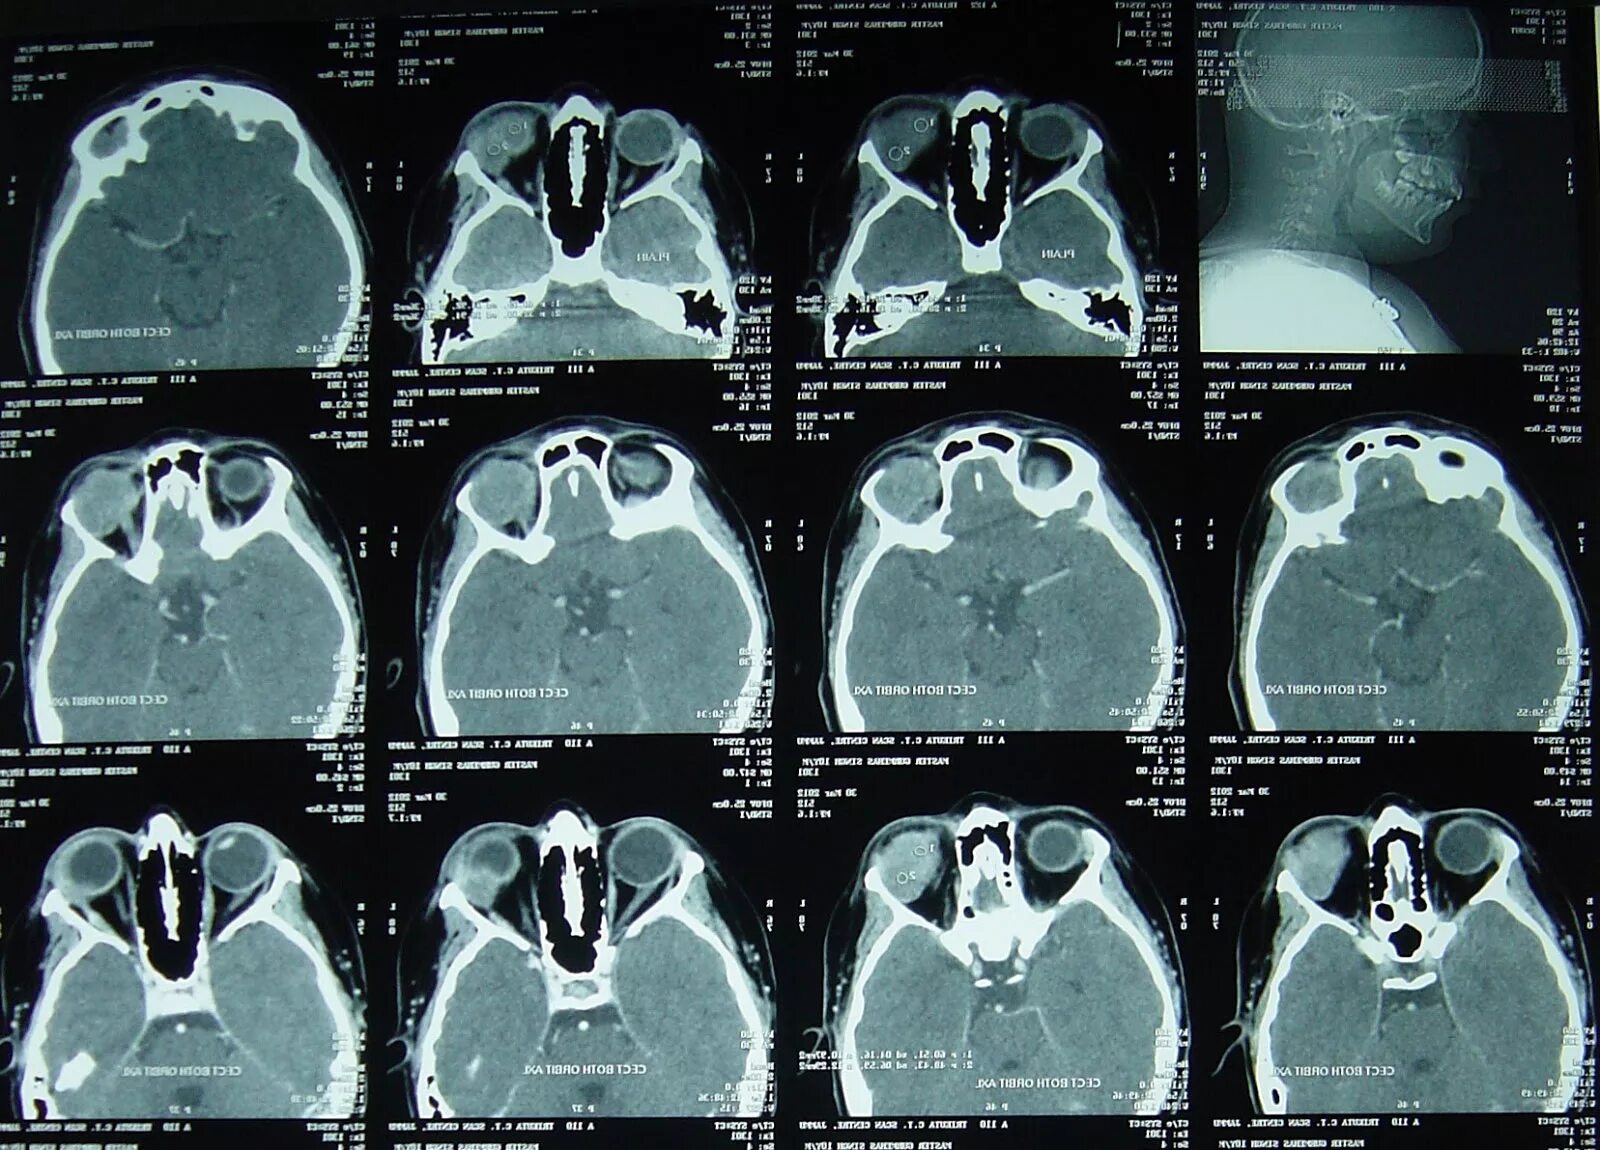

Томограмма глаза